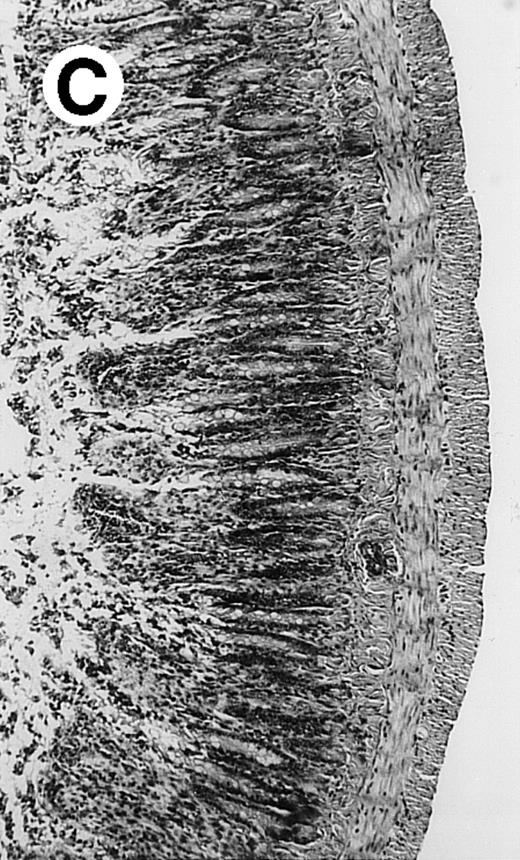

Pathologic findings in the small and large intestine were strikingly different depending on the treatment group. Figure 2A shows a representative pathologic sample from an animal assigned to the control group. Marked thinning of the bowel wall and extensive areas of epithelial cell sloughing was noted. Animals randomized to rhG-CSF treatment had minimal improvement in histologic findings with focal regions of preserved epithelium (Fig2B). Animals randomized to the rhIL-11 group showed substantial improvement with thickening of the epithelial layer and preservation of mucosal cell integrity (Fig 2C). Animals receiving both rhG-CSF and rhIL-11 had the most favorable histologic findings with normal mucosal thickness, minimal inflammatory changes, and preserved tissue architecture (Fig 2D). The composite analysis of the gastrointestinal pathology is provided in Table 1.

Histopathology of small intestinal mucosa cut in transection from an animal in each treatment group (study day 8). The upper panel (row 1) is a low power view (original magnification × 57); the lower panel (row 2) is a high power view (original magnification × 144). Note the diffuse thinning and necrosis of the mucosa with sloughing of intestinal epithelial cells in the control animal (A). There is progressive recovery of the thickness of the mucosa, reduction in inflammatory changes, and improved epithelial architecture with rhG-CSF (B), rhIL-11 (C), and combination therapy with rhG-CSF+IL-11 (D).

rhIL-11 has been shown to have marked effects on gastrointestinal epithelial surfaces. rhIL-11 blocks apoptosis of epithelial cells exposed to radiation and chemotherapy in mice.22 rhIL-11 is protective in a variety of mucositis models and in models of intestinal inflammation.4,23,24 rhIL-11 has been shown to prolong the G-0 phase of growth of intestinal epithelial cells. The precise mechanism of action is not known, but it has been observed that rhIL-11 decreased pRB (retinoblastoma protein) phosphorylation (an important signaling event in cell cycling) within intestinal epithelial cells.32 rhIL-11 has protective effects on gastrointestinal mucosa in transgenic rats, which possess HLA-B27 antigens.4These animals develop an inflammatory colitis that is similar in many respects to human inflammatory bowel disease. rhIL-11 treatment in these animals decreases intestinal inflammation and chronic diarrhea. Based on these preclinical findings, rhIL-11 is currently in clinical trials in both inflammatory bowel disease and chemotherapy-induced mucositis.33 The remarkable capacity of rhIL-11 to protect the gastrointestinal mucosal integrity after chemotherapy is apparent in the current series of experiments (Fig 2).